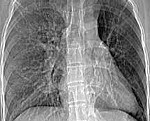

J43.0 Синдром Мак-Леода